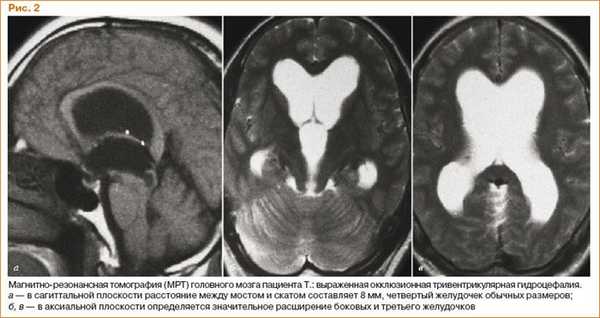

Первый - окклюзионная гидроцефалия, когда отток ликвора нарушается из-за какого-то механического препятствия.

При этом ликвор продолжает вырабатываться, а вышележащие отделы начинают расширяться. Это окклюзионные формы гидроцефалии. В результате возникает сдавление мозга, бесконтрольный рост головы, нарушается развитие малыша.

Остальные формы опасны тем, что происходит прорыв крови в желудочки мозга с формированием тромбов внутри желудочков и механическая закупорка этими тромбами узких отверстий. В результате расширяется либо 3 либо 4 желудочка (можно встретить термин тривентрикулярная или тетравентрикулярная гидроцефалия - в зависимости от количества расширенных полостей).

Закрытая, или окклюзионная гидроцефалия является следствием закупорки ликворных путей в мозге (лат. occlusus - запертый). Чаще это симметричная гидроцефалия, в равной степени затрагивающая оба полушария и подкорковые структуры и возникающая при аномалиях развития водопровода мозга либо его сдавлении опухолью субтенториальной локализации, например в области 3-го или, чаще, 4-го желудочка. Окклюзионная гидроцефалия обычно ведет к переполнению ликвором и расширению желудочковой системы (иными словами, это внутренняя гидроцефалия). Субарахноидальные пространства при ней бывают сужены так, что на КТ они не определяются. Часто внутренняя гидроцефалия приводит к столь высокому внутричерепному давлению, что это может представлять серьезную угрозу для жизни из-за прекращения мозгового кровотока. При синдроме Брунса возникают приступы резкого подъема внутричерепного давления.